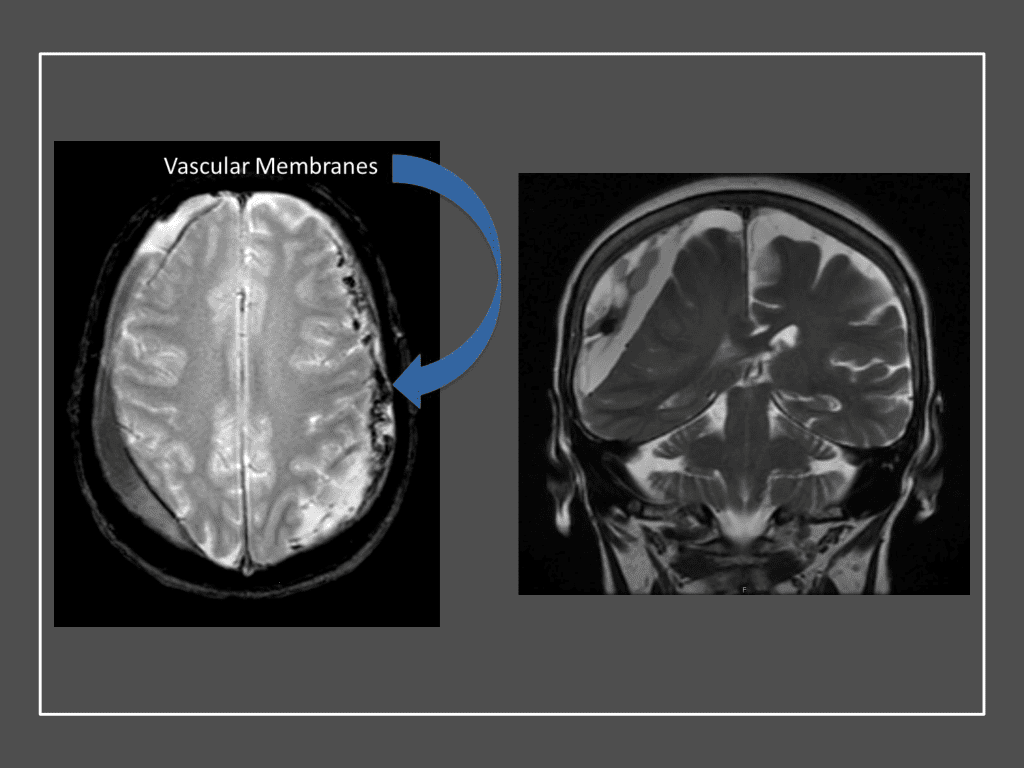

A woman in her 80s developed mild dizziness and headache following incidental trauma working in her garage one day. She presented several weeks later to the ER and was diagnosed with bilateral subdural hematomas, which were initially managed with observation, low dose Decadron, considering the mildness of symptoms, advanced age, and history of CLL with thrombocyptopenia (<100k). Over the next 4 weeks, the collections remained relatively stable with evidence of slight growth (10 to 12 mm thickness, and 2 mm right to left shift) on NCT (Figure 1. A and B).

Figure 1. A) 6 weeks post mild trauma B) 4 weeks post mild trauma demonstrates stable subacute subdural collections with mild growth and sulcal effacement.